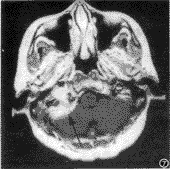

图5 左侧神经鞘瘤,横轴位T2WI示左侧颈静脉孔内病灶呈高信号,无流空(黑箭)

图6 与图5同一病例相邻层面增强后,左侧颈静脉孔上后方病灶明显强化(黑箭)

图7 右侧脑膜瘤,横轴位增强后T1WI,右侧颈静脉孔区病灶宽基底附着于小脑半球前方(黑箭),并伸入颈静脉孔内(箭头),呈明显均匀强化

颈静脉孔区病变种类较多,鉴别诊断包括血管异常、神经鞘瘤、脑膜瘤以及其他化学感受器瘤等。颈静脉孔区血管异常中最常见系颈静脉球高位,临床上亦表现为搏动性耳鸣;CT显示鼓室底壁骨质缺失,MRI则显示此颈内静脉因血流缓慢而呈高信号,局部无占位效应[3]。颈静脉孔区神经鞘瘤来源于后组颅神经,临床上以声音嘶哑为最突出症状;CT常见颈静脉孔腔扩大,边缘光滑;稍大的肿瘤常发生囊变,一般不侵犯中耳,常将颈动脉向前内、颈内静脉向后推移[4]。本文另选用1例经手术病理证实的来源于舌下神经的神经鞘瘤,MRI显示病灶位于颈静脉孔上下,T1WI呈近等信号,T2WI呈高信号,无流空现象,强化明显(图5、6)。颈静脉孔区脑膜瘤基底在硬膜,边界甚清,CT可见钙化并呈较明显的强化。本文亦另选用1例经手术病理证实的脑膜瘤,MRI显示病灶位于颈静脉孔内及岩骨尖下方,以宽基底与小脑紧贴,T1WI呈等信号,T2WI呈稍高信号,亦无流空表现,强化明显而均匀(图7)。颈动脉体瘤、迷走神经节瘤与颈静脉球瘤同属化学感受器瘤,均富血供,可见流空现象,增强后明显强化。但颈动脉体瘤起源于颈动脉体,它一般位于上颈部,造成颈动脉分叉明显撑开。迷走神经节瘤最常起源于迷走神经节内的球组织,在咽旁间隙内生长,多向下扩展,但少数也可向上延伸至颈静脉孔区,它多使颈内外动脉同时移向前内方从而与颈内静脉分开[5]。若进一步行DSA检查,上述三类化学感受器瘤均有明显肿瘤染色,且主要由颈外动脉系统供血,但三者的具体供血动脉又各有不同,有利于互相鉴别[6]。